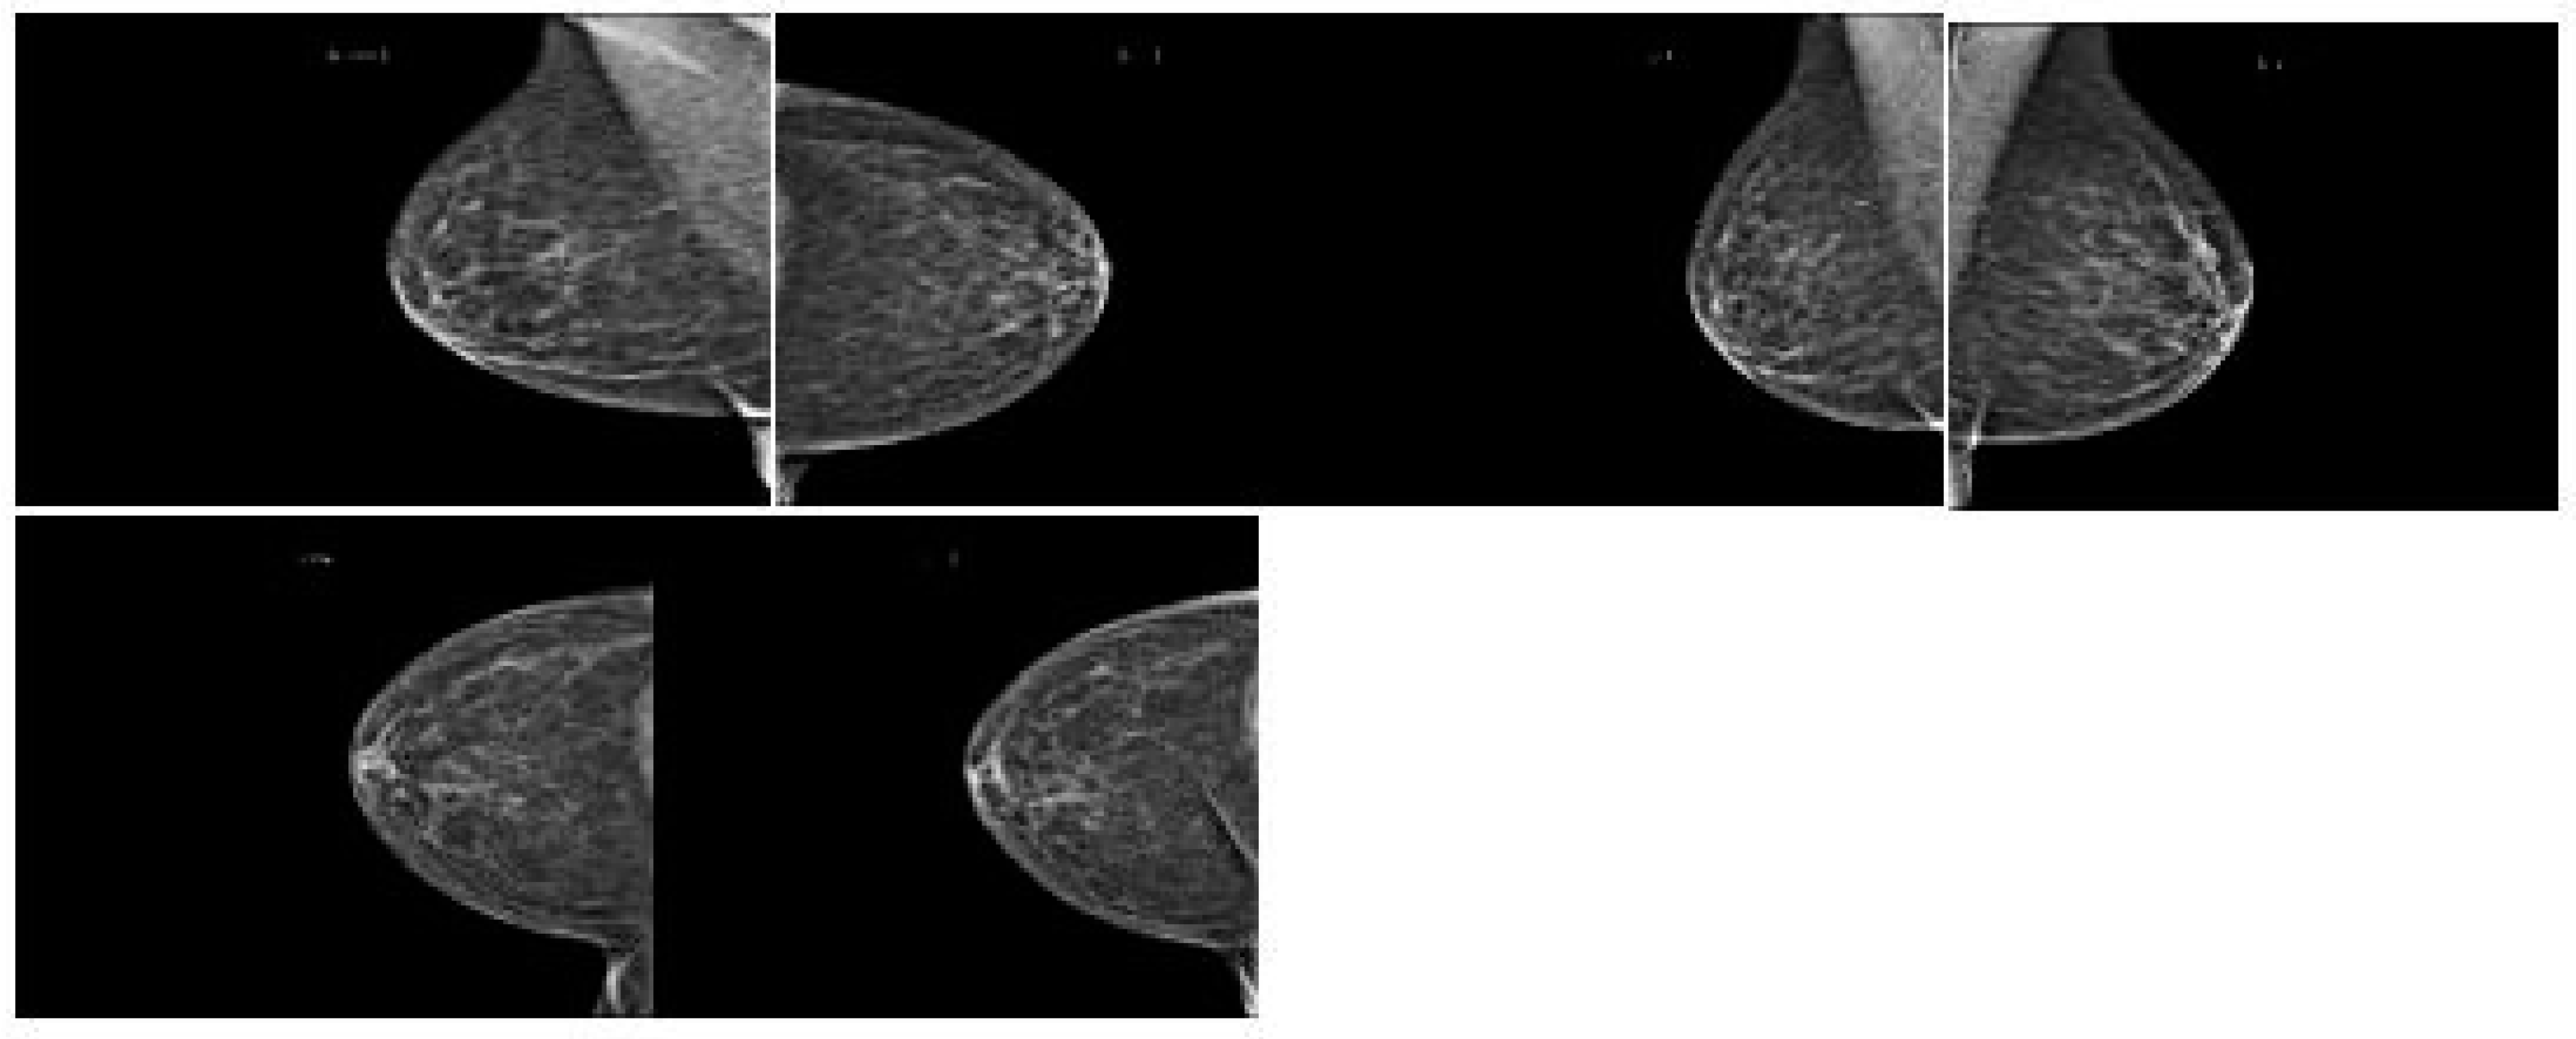

Figure 3 shows how breast cancer on mammograms can vary depending on stage, size, and location. Radiologists examine for abnormalities and patterns to detect breast cancer. Common findings include masses, microcalcifications, architectural distortions, asymmetries, spiculated borders, and nodules. Masses, microcalcifications, and architectural distortions are early signs of breast cancer, while microcalcifications are tiny calcium deposits in breast tissue. Figure 4 show the architectural distortions. These may appear as irregularities in the breast’s structure, while asymmetries indicate differences in appearance between the left and right breasts. Speciated borders, jagged or spiky edges, and nodules are small rounded masses that are assessed for potential malignancy.

Figure 4. Breast cancer look on mammography.